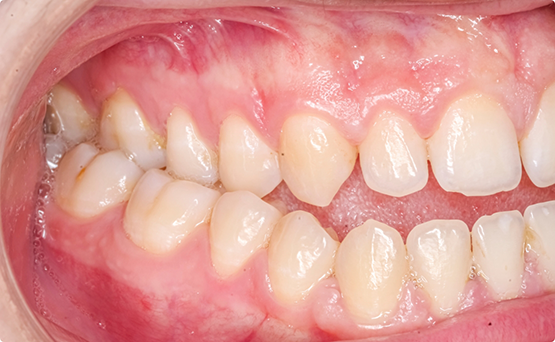

Crossbite

There are two types of crossbite. One type occurs at the back of the mouth (posterior crossbite); it is when the upper back teeth bite down inside the lower back teeth. The other type occurs at the front of the mouth (anterior crossbite); it is when the upper front teeth sit inside the lower front teeth. Both types of crossbite can lead to jaw pain and damage to the teeth. Invisalign aligners can correct your crossbite with the help of your orthodontist.